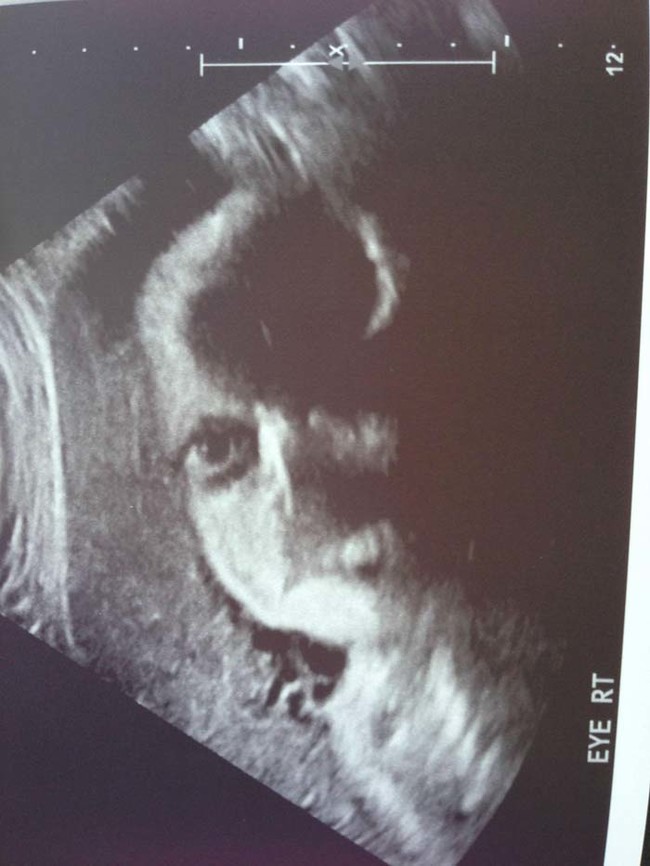

เดี๋ยวนี้ยามตั้งครรภ์คุณแม่เกือบทุกคนก็นิยมอุ้มท้องป่อง ๆ ไปให้คุณหมอทำอัลตราซาวด์ จะได้เช็กดูว่าเจ้าตัวน้อยข้างในอยู่สบายแข็งแรงดีหรือเปล่า แถมยังได้จะเห็นไปหน้าเค้าโครงใบหน้าลาง ๆ ของเจ้าหนูด้วย ดูแค่เงาก็เดาไปกันใหญ่แล้วว่าเหมือนใครมากกว่ากัน จนอดใจไม่ไหวอยากรีบคลอดออกมาให้เห็นหน้าลูกน้อยตัวจริงเร็ว ๆ แต่ถ้ามาเจอ 13 รูปอัลตราซาวด์สุดสยอง ที่เรานำมาฝากจากเว็บไซต์ boredomtherapy เหล่านี้เข้าไปหน่อยล่ะก็... บางทีคุณอาจไม่แน่ใจแล้วล่ะว่า นี่ใช่ลูกฉันจริงหรือเปล่า !!

ถึงจะรักเด็กแค่ไหน แต่ถ้าคุณขวัญอ่อนเราขอเตือนกว่าอย่าเลื่อนลงไปดูดีกว่านะ...